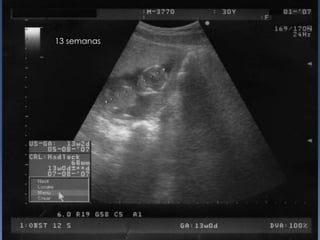

13 semanas